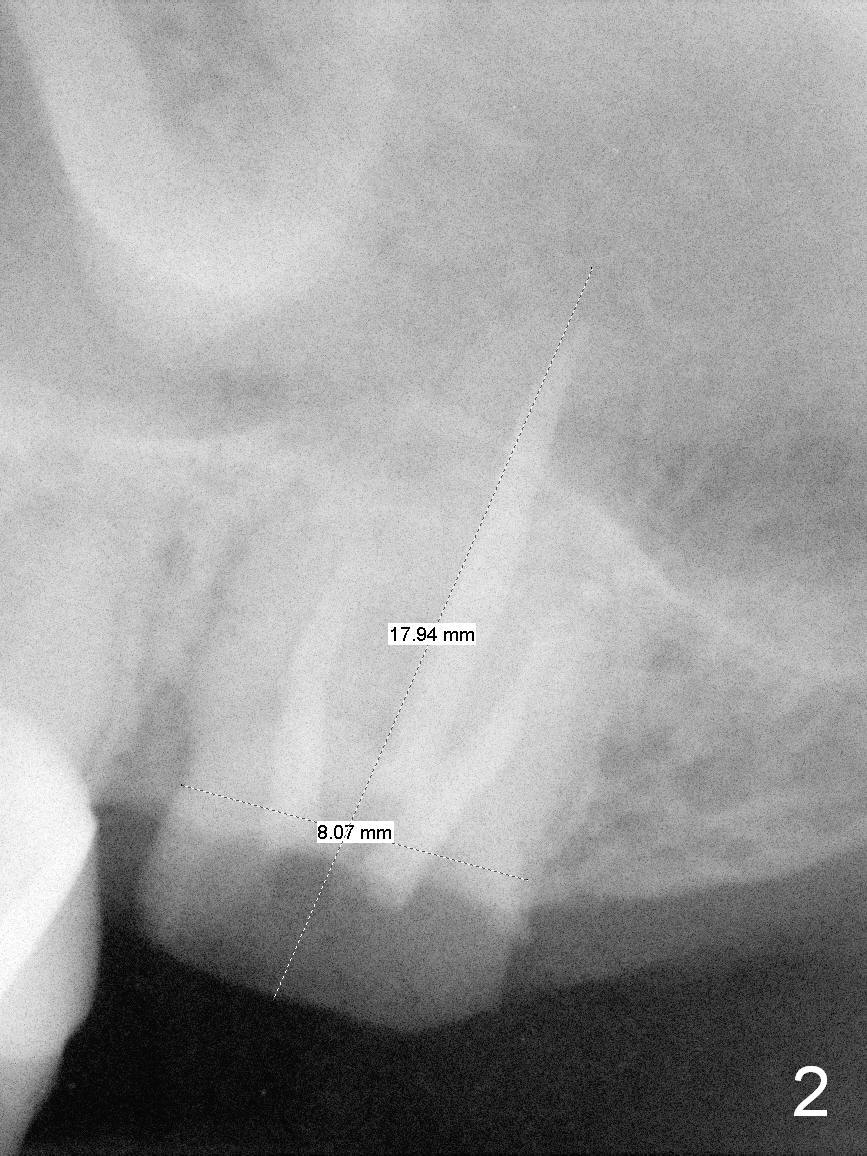

Probably Single Socket

The tooth #15 of a 62-year-old man (CY) has been fractured for 4 years (Fig.1).  The 3 roots (MB, DB and P) appear to be approximated each other (Fig.1,3,4) so that when the tooth is extracted (using a surgical handpiece for sectioning), the socket should be single and large.  Treat the socket with Clindamycin.  If the socket proves to be flat on the top, the thickness of the sinus floor is approximately 2 mm.  If the bone is not so tough, use osteotomes to do sinus lift; otherwise use drills.  The depth of osteotomy should be tightly monitored.

PA shows that the depth of the osteotomy is approximately 17 mm (Fig.2), whereas CT 14 mm (Fig.3,4).  Intraop measurement will determine the depth.